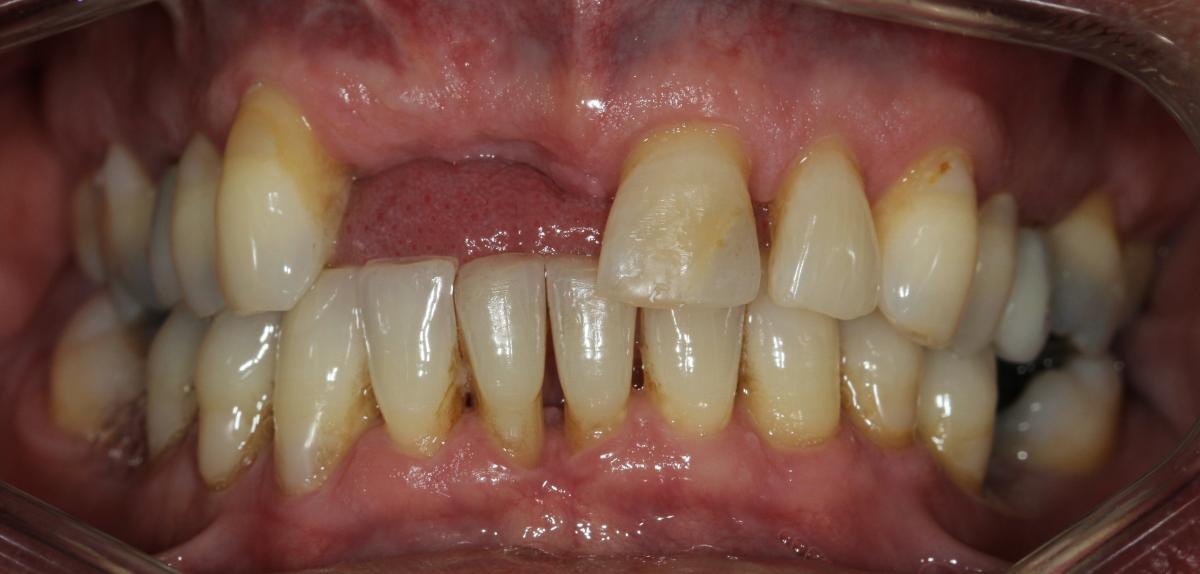

Missing teeth and loose dentures make many people avoid social settings because they are too self-conscious about their appearance. Current dental procedures, however, replace everything from a single missing tooth to a completely missing arch. Ask your dentist or dental specialist about the different dental options that are available to you. Don’t let another day go by without taking this important first step to restoring your confidence and your smile!